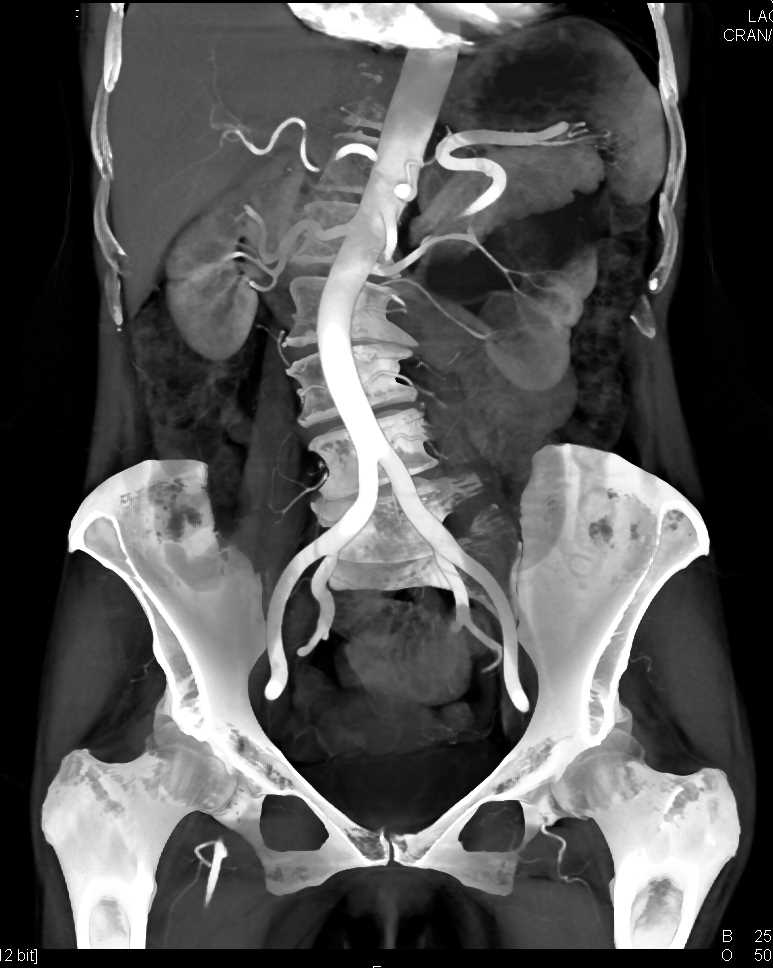

Parapelvic Cysts Left Kidney